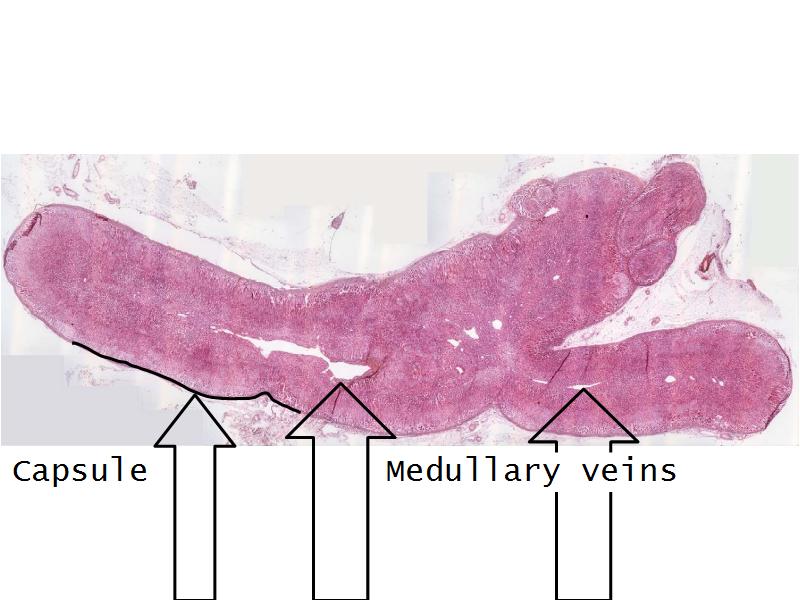

- Slide 56: Adrenal glands

Adrenal glands

Capsule

Cortex - how many zones?

Medulla

Hormones of each?